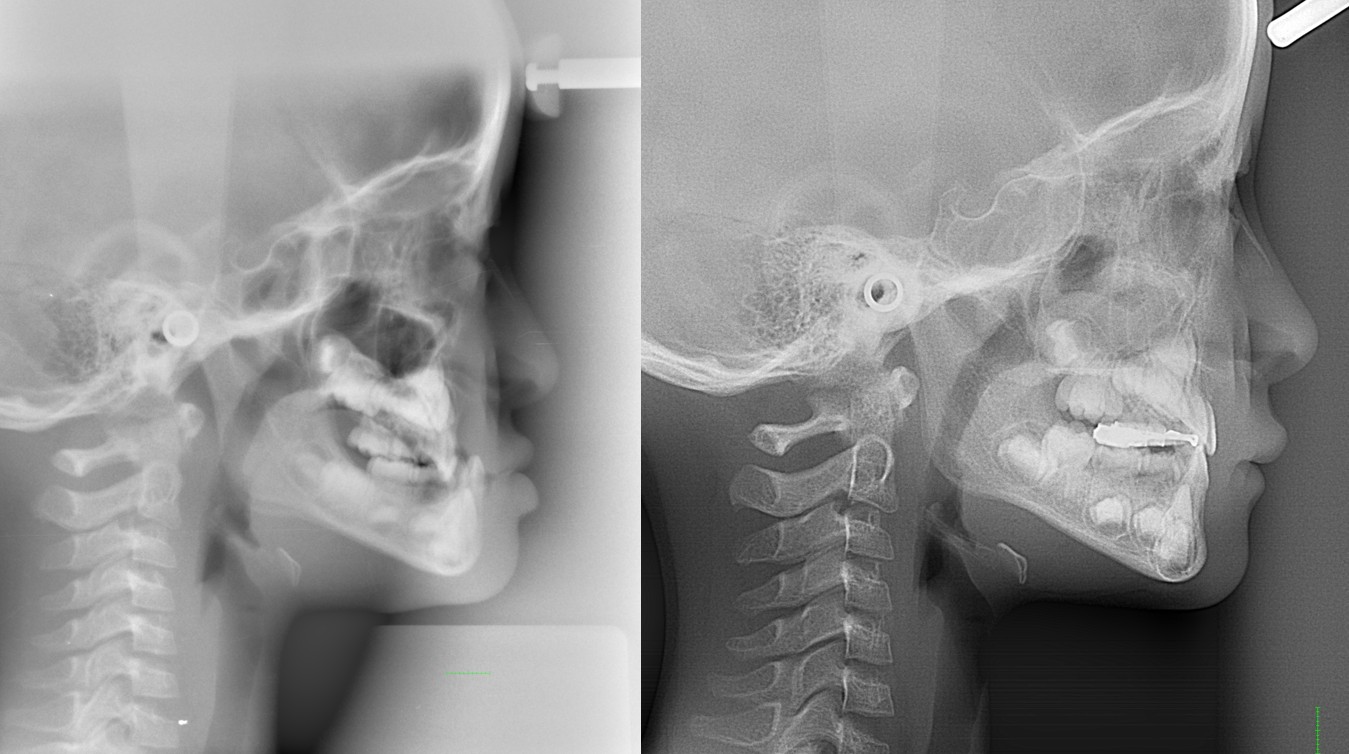

下の顎が出ている(反対咬合:いわゆる受け口)

反対咬合:いわゆる受け口など

・主訴:受け口である

・診断:下顎前突

・年齢:25歳

・使用した主な装置:マルチブラケット装置

・抜歯部位:なし

・治療期間:24か月

・通院回数:24回

・費用の目安:矯正料金として60万+税金。診断料金6.5円+税金。調整処置料金:月3000円+税金を24回で7万2千円+税金。 総額 810.700円。